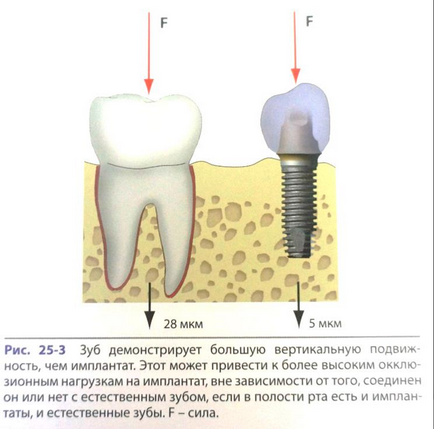

Az implantátumok, ellentétben a fogak kisebb mobilitást. Pontosan. Azt nem mondhatjuk, hogy azok teljesen fix a csontban.

Ez a tézis nem igényel részletes magyarázatot, mind le Misha. Ami még fontosabb -, hogyan használjuk ezt a tudást. Engedheti meg magának, csak hogy rövid részeit az alapvető munka.